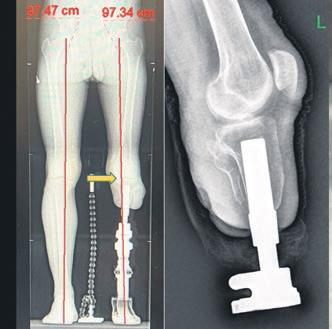

Türkiye'de ilk kez uygulanan yöntemi Prof. Dr. Kara, şöyle anlattı: "Klasik soket protezlerin yol açtığı ağrı, yara ve yürüme zorluklarına bir alternatif sunan 'osseointegrasyon yöntemi' ampütasyon hastalarına umut veriyor. Türkiye'de yeni nesil osseointegrasyon protezini uygulayan ilk merkeziz. Bu yöntemle hastalar adeta kendi bacaklarıyla yürüme hissine kavuşuyor."

Bu protezlerin yapıldığı uzuvlar hakkında da bilgi veren Prof. Dr. Kara, yöntemin uyluk, kaval kemiği, dizüstü ve dizaltı gibi bölgelerin yanı sıra üst kol ampütasyonlarında da başarıyla uygulandığını aktardı.

Osseointegrasyon protezinden kimlerin faydalanabileceğine de değinen Prof. Dr. Kara, yöntemin en çok daha önce soket protez kullanmış ancak çeşitli sorunlar yaşamış genç ve aktif hastalara önerildiğini söyledi. Prof. Dr. Kara "Ciltte yara oluşumu, yürüyüş sırasında ağrı, uyumsuzluk nedeniyle erken yorulma gibi sorunlarla bize gelen hastalarda bu yöntem oldukça etkili. Klasik protezlerle sadece birkaç dakika yürüyebilen hastalar, bu yeni sistemle hayata tekrar karışabiliyor" dedi.